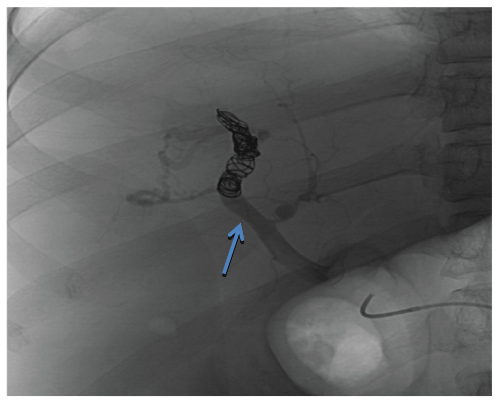

On the third hospital day, he developed hematemesis. Endoscopy revealed small, non-bleeding esophageal varices and a bleeding gastric varix. The arterio portal fistula was embolized by placing multiple coils within the distal right hepatic artery via an aortic approach. Flow through the fistula was greatly reduced but it could not be completely obliterated and remained patent because of its large size (Figure 2). A right hepatic lobe resection to remove the fistula was planned but the procedure was cancelled after the patient's clinical status deteriorated further and he was transferred to the intensive care unit for possible sepsis. His hospital course was complicated by recurrent variceal bleeding, multiple respiratory infections, sepsis and intractable as cites and he expired after a protracted 3-month course. The original cause of the fistula remains unknown as he had never experienced abdominal trauma, malignancy or prior liver biopsy.

Figure 2: Post-coil embolization angiogram of the arterio-portal fistula. Flow through the fistula was greatly reduced but the fistula remained patent. Blue Arrow: Fistula between the right hepatic artery and right portal vein.